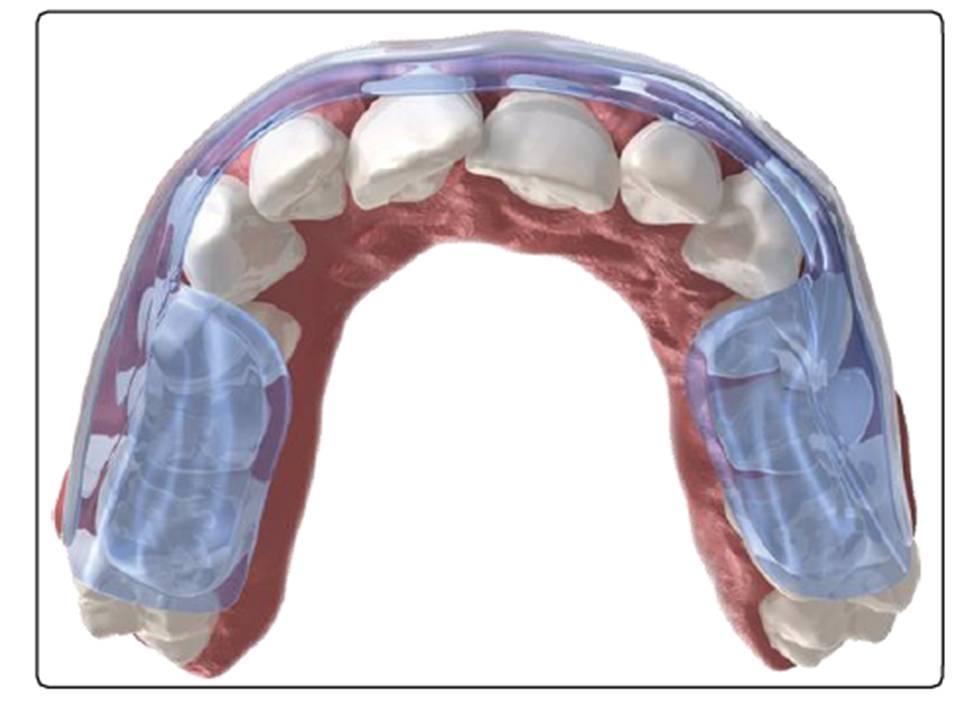

水平衡咬合板的流體系統可實現完美的咬合平衡,

通過以微創方式進行TMJ治療可保持穩定性。

通過允許肌肉自身自動運作

將下巴重新定位到自然效果最佳的位置。對於TMJ疼痛

處理,恢復這種平衡至關重要。

與其他可用的牙夾板不同,水平衡咬合板自動調節

咬合夾板是一種TMJ治療,可使身體解開咬傷

扭曲並建立最佳的系統功能和平衡。

水平衡咬合板的流體系統可實現完美的咬合平衡,

通過以微創方式進行TMJ治療可保持穩定性。

通過允許肌肉自身自動運作

將下巴重新定位到自然效果最佳的位置。對於TMJ疼痛

處理,恢復這種平衡至關重要。

與其他可用的牙夾板不同,水平衡咬合板自動調節

咬合夾板是一種TMJ治療,可使身體解開咬傷

扭曲並建立最佳的系統功能和平衡。